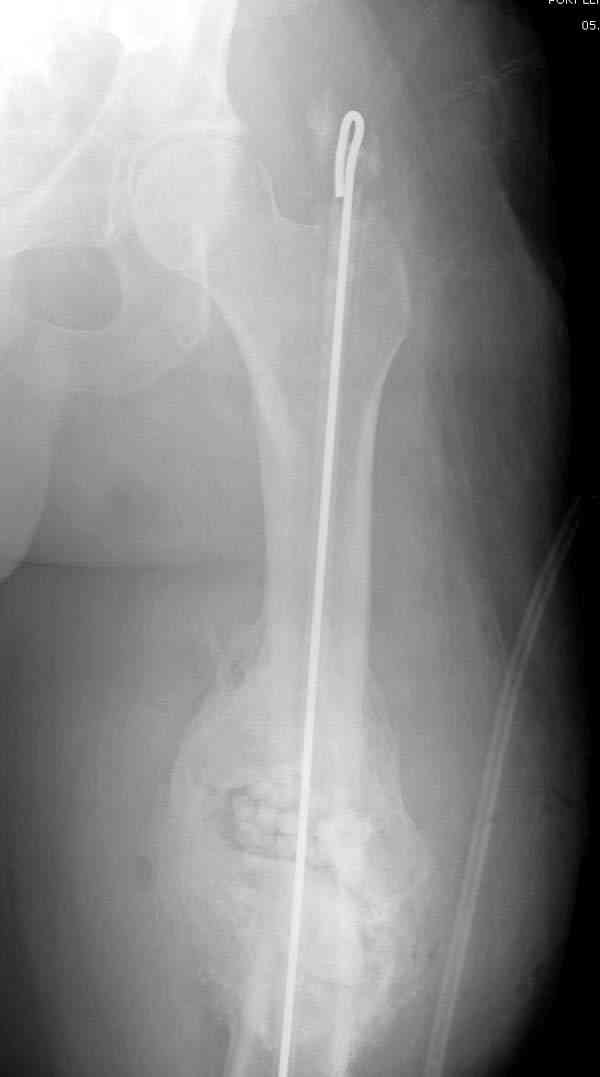

После определения длины канала берется 3мм длинная проволока, обычно "long guided wire" от интрамедуллярного набора, концы загибаются, ее

вставляют в трубку, трубку заполняют цементом с антибиотиком.

старый снтибиотический гвоздь

ренгенограмма инфицированного бедра со старым

антибиотическим гвоздем